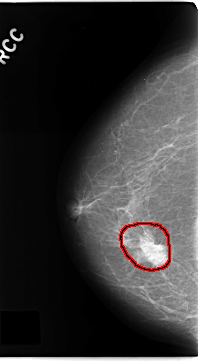

C_0181_1.RIGHT_CC

RIGHT_CC LINES 4688 PIXELS_PER_LINE 2568 BITS_PER_PIXEL 12 RESOLUTION 50 OVERLAY

FILE: C_0181_1.RIGHT_CC.OVERLAY

TOTAL_ABNORMALITIES 1

ABNORMALITY 1

LESION_TYPE MASS SHAPE IRREGULAR MARGINS SPICULATED

ASSESSMENT 5

SUBTLETY 5

PATHOLOGY MALIGNANT

TOTAL_OUTLINES 1

BOUNDARY